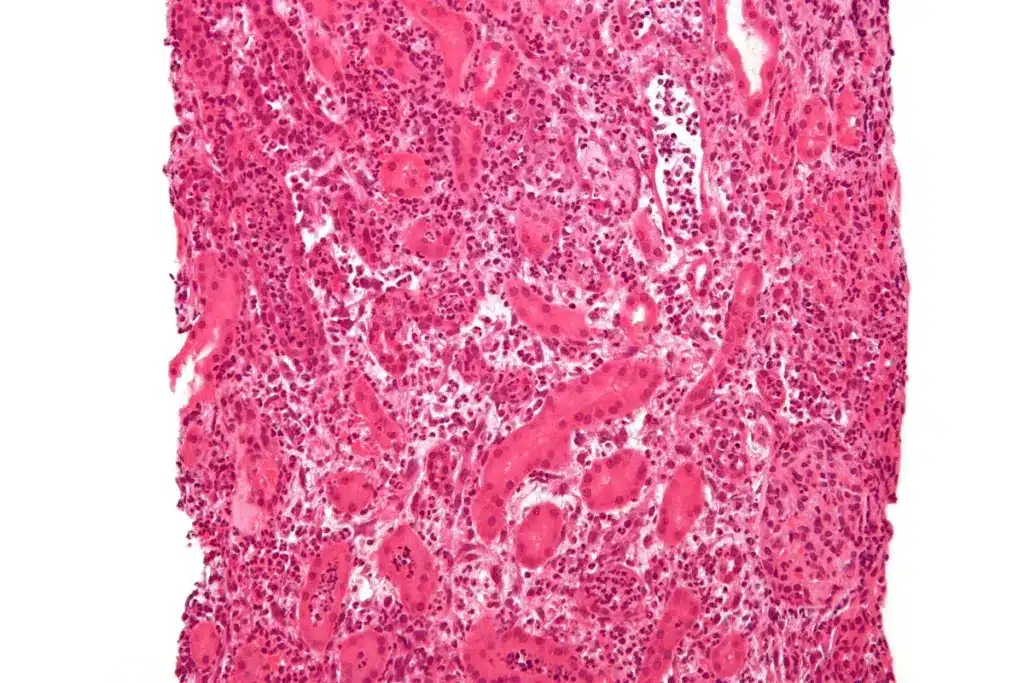

Pyelonephritis is when the kidney’s renal pelvis and tissue get inflamed due to bacteria. If not treated quickly, it can harm the kidneys a lot. The infection usually starts in the lower urinary tract and moves up to the kidneys. Knowing the causes and risk factors is key to preventing and treating it early.

- Infection and inflammation of the kidney tissue

- Damage to the urinary tract lining

- Possible abscess formation